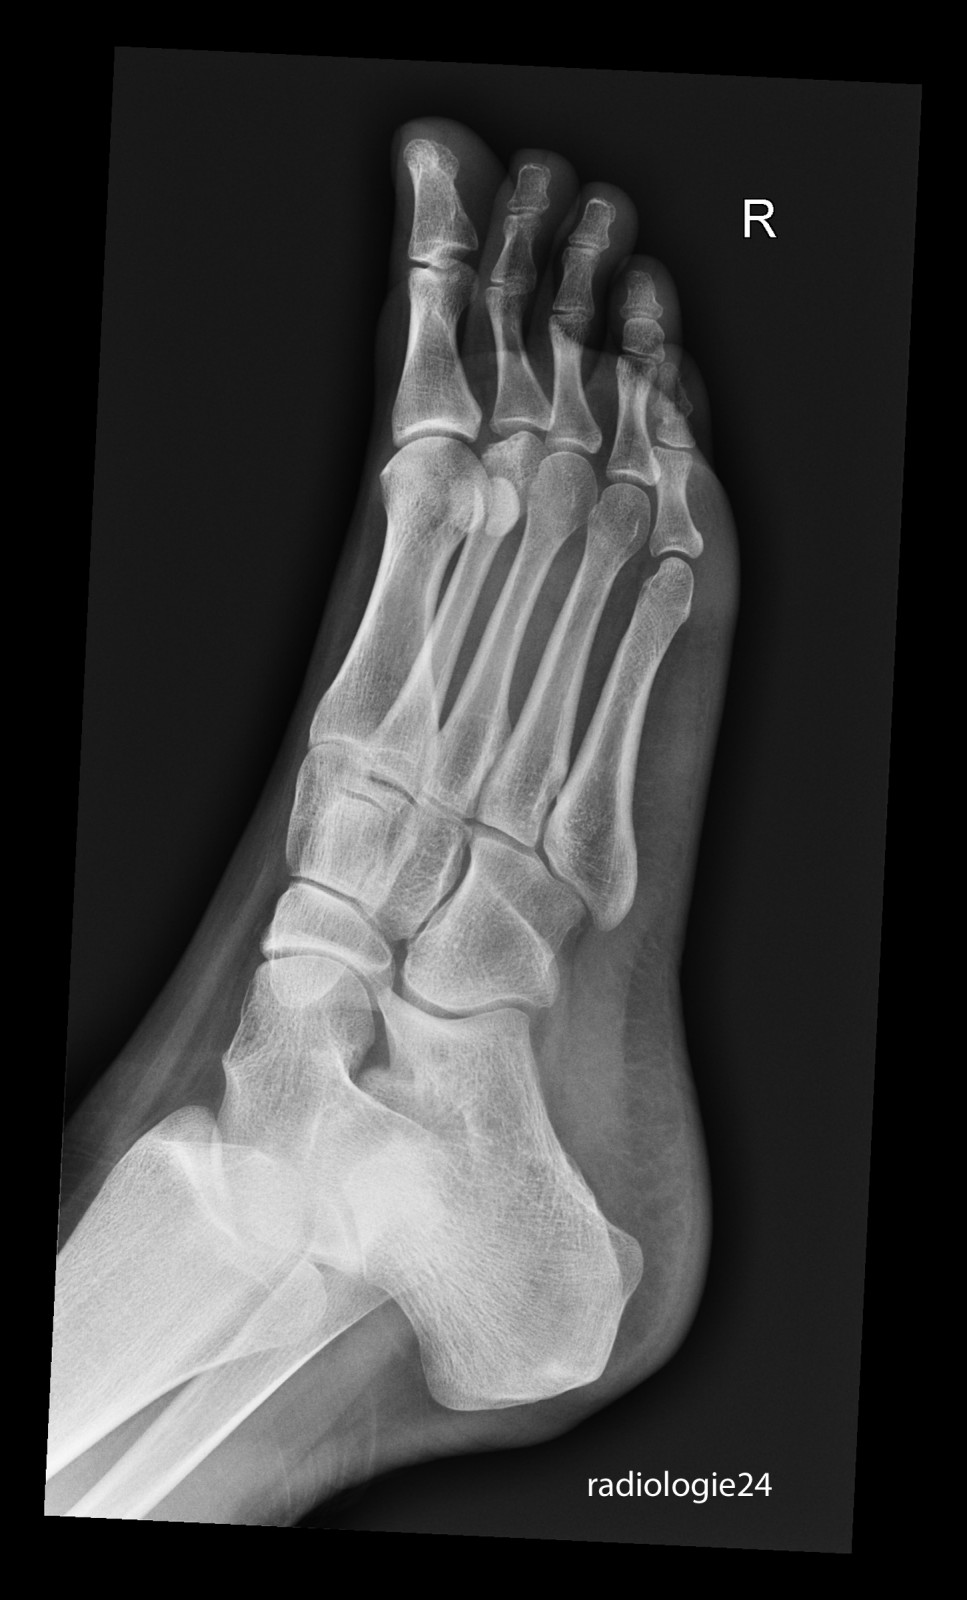

Röntgenfall des Monats November 2017 mit Auflösung

18 jährige Patientin Klinische Angaben: Schmerzen Vorfussbereich. Kein Trauma erinnerlich.

Bild vergrössern

Link zur Auflösung mit ausführlichem Befund

https://www.radiologie24.ch/radiologie-mediathek/roentgenfall_des_monats